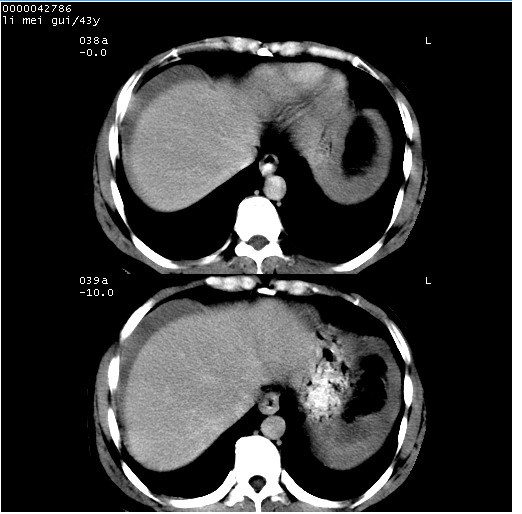

| 患者,男,43岁。突发腹痛2小时,面色苍白,难以平卧。自述近期无明确外伤史,为摩托车驾驶员。 腹部b超检查:脾脏中上极回声异常,肿瘤待排。 临床诊断:腹痛原因待查。 上中腹部ct轴位平扫+增强扫描(层厚10mm,螺距1.0,重建间隔10mm),图像如下: ![]() ![]() ![]() ![]() ![]() ![]() ![]() ![]() ![]() ![]() ![]() ![]() ![]() ![]() ![]() ![]() ![]() ![]() ![]() ![]() ![]() ![]() ![]() ![]() ![]() ![]() ![]() ![]() ![]() ![]() ![]() ![]() ![]() ![]() ![]() zrs发言:支持脾破裂 wwp发言:支持脾破裂并腹水。 xulianj发言:脾脏肿瘤破裂可能性大 zsl6918发言:不像肿瘤出血,考虑还是与外伤后引起的慢性出血有关 zzyy发言:平扫见肝周及脾周积液,脾内密度不均。脾内肿瘤较少见。还是外伤性脾破裂。 沈丘东方医院发言:脾门区一个不均匀强化病灶与其周液体相连多考虑脾占位破裂出血 yixianman001011发言:脾破裂并腹水是可以肯定的,具体原因多以肿瘤性破裂出血,脾脏淋巴瘤可能性大. 结果: 术后,经详细询问患者,其仔细回忆:一月前骑摩托时左侧腰部与别人有“轻微”触碰,因责任在自已,当时又无明显不适,未引起注意。 临床术后诊断:脾破裂并失血性休克(1.外伤性迟发性脾破裂。2.脾脏肿瘤破裂?) 术后标本病检:脾破裂并出血,未见明显肿瘤成份。 原贴地址:http://www.radinet.com.cn/forum_view.asp?forum_id=4&view_id=34070 |